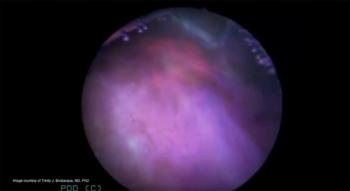

In this video, Trinity J. Bivalacqua, MD, PhD, presents the case of a 63-year-old man with history of carcinoma in situ found to have low-grade Ta non-muscle invasive bladder cancer.

Based on recent developments with blue light cystoscopy, the use of white light cystoscopy alone is now considered suboptimal as a diagnostic tool.

More evidence is needed before blue light cystoscopy becomes the standard of care for diagnosis and treatment and renders white light cystoscopy obsolete.

Fluorescent blue light cystoscopy improves 3-year recurrence-free survival rates in patients with recurrent bladder tumors compared to white light cystoscopy, and researchers believe its use should be expanded.